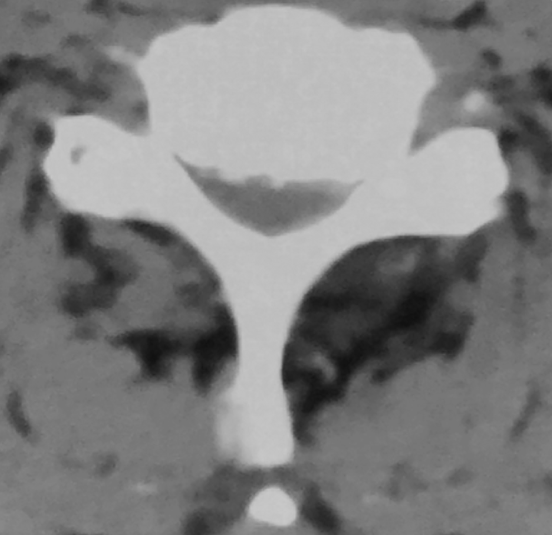

CT:C5-6

软组织窗

行颈前路减压植骨融合内固定术,由于患者钩椎关节增生严重,术中应用超声骨刀对对骨赘进行切除。

超声骨刀辅助下切除患者左侧增生的钩突,手术过程顺利